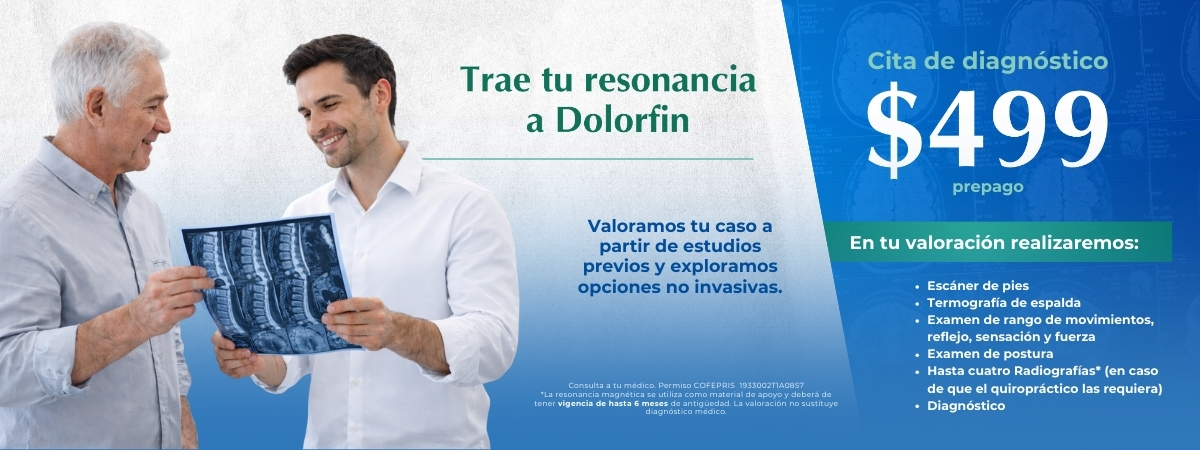

¿Qué es Dolorfin?

Red de clínicas especializadas en el cuidado de tu columna y sistema nervioso

Quiropráctica clínica, fisioterapia, terapias manuales y acupuntura

Valoración profesional + plan 100% a tu medida para moverte mejor y vivir mejor

Tratamientos quiroprácticos personalizados

El éxito y duración de un tratamiento consiste en valorar adecuadamente tus condiciones. Si es la primera vez que asistes con un quiropráctico es importante agendar una cita de valoración donde se realice revisión de postura, columna vertebral, reflejos de sensación y fuerza, rangos de movimiento y postura por computadora. De este modo nuestros especialistas podrán saber si está en nuestras manos apoyarte. Asiste a una valoración y recuerda que puede durar aproximadamente 90 min.